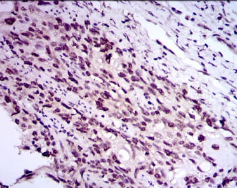

IHC    1/200 - 1/1000